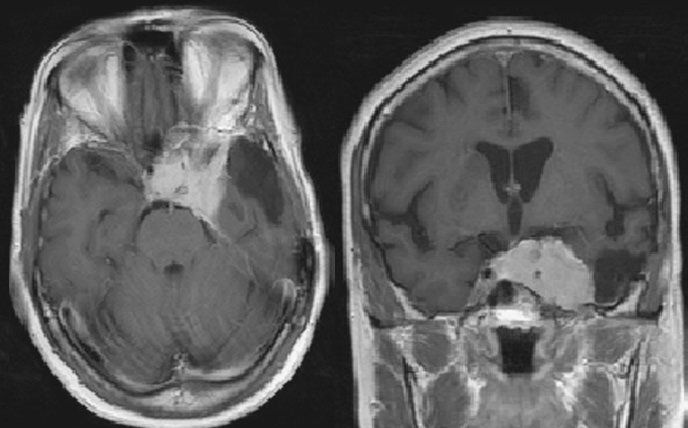

Как обнаружить менингиому височной области с помощью МРТ